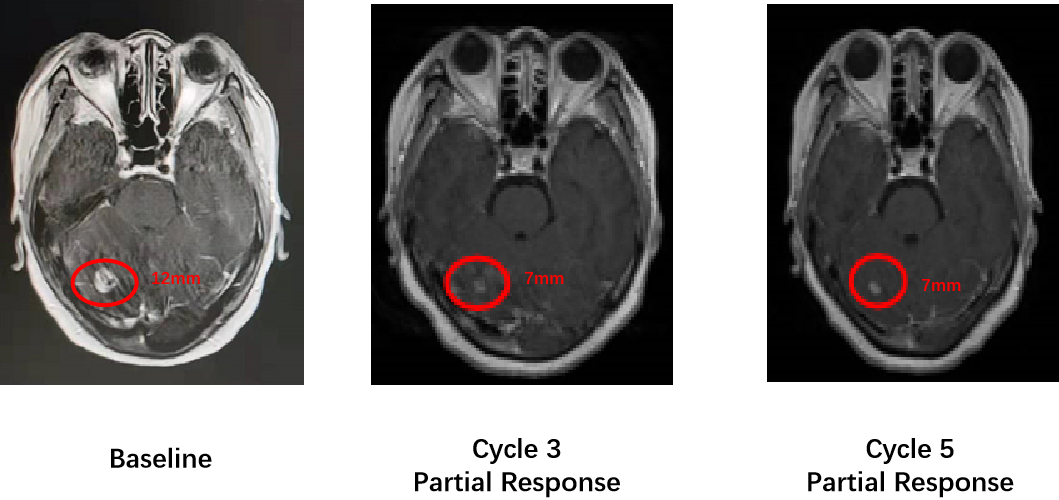

此外,这款药物还具有强大的入脑活性,在8例基线有脑转移的受试者中,3例达到部分缓解(PR),颅内ORR达到37.5%。

一位幸运的EGFRex20ins患者接受320mgQD剂量治疗后,首次肿瘤评估时脑病灶较基线缩小5mm。